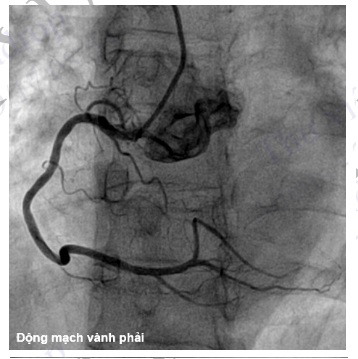

Hình 4.94. Chụp ĐMV phải ở tư thế nghiêng trái (LAO 30)